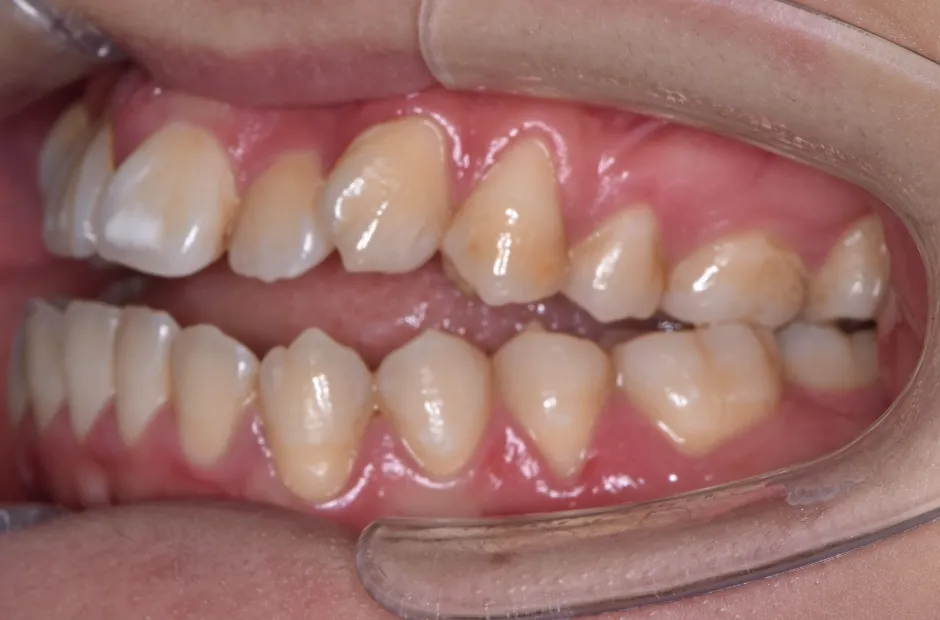

叢生

| 診断名・主訴 | 叢生 |

|---|---|

| 年齢・性別 | 43歳・女性 |

| 治療期間・回数 | 2年7か月 27回 |

| 治療に用いた主な装置 | 舌側矯正 |

| 抜歯部位 | 両顎4,4 |

| 治療費 | 100万円(税抜) |

| リスク・副作用 | 装置による違和感・疼痛・歯肉退縮・歯根吸収・虫歯のリスクなど |

治療前

治療中

治療後